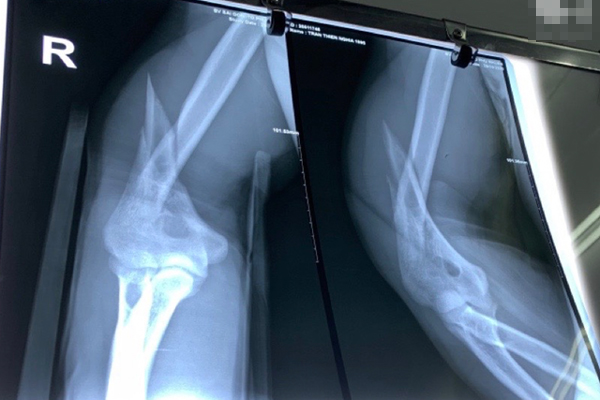

Giải thích về nguyên nhân tại sao chúng ta không nên lấy ráy tai? Bác sĩ Trần Lượng Vũ trả lời: "Tai ngoài là bộ phần gồm xương mềm (còn gọi là sụn) và xương cứng. Ráy tai thường tích tụ ở khu vực sụn và rất ít ở khu vực xương cứng. Khi chúng ta sử dụng tăm bông lấy ráy tai, hành động này khiến ráy tai vô tình bị đẩy sâu vào bên trong giống như bạn đang cố nhét một cái nút chai, điều này sẽ khiến ráy tai ngày càng tích tụ dày đặc hoặc thậm chí nguy hiểm hơn là gây thủng màng nhĩ. Có một trường hợp bệnh nhân do lấy ráy tai bằng tăm bông khiến ráy tai bị đẩy sâu vào bên trong, gây ra hiện tượng viêm tai giữa mạn tính, xâm lấn vào trong xương, dẫn đến tê liệt dây thần kinh mặt".